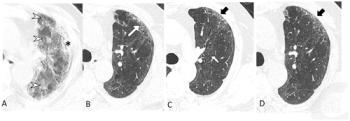

Recently published research revealed that coronary computed tomography angiography (CCTA) exams performed with dual-source CT were completed 22 minutes faster and had a nearly 28 percent higher frequency of good or excellent image quality in comparison to CCTA exams performed with single-source CT devices.